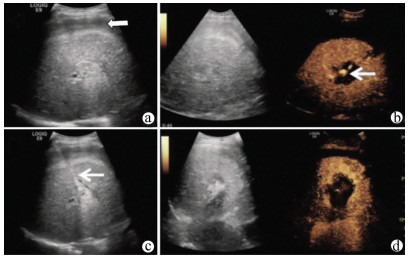

Guideline for ultrasonic diagnosis of liver diseases

Chinese Society of Ultrasound in Medicine, Oncology Intervention Committee of Chinese Research Hospital Society, National Health Commission Capacity Building and Continuing Education Expert Committee on Ultrasonic Diagnosis

2021, 37(8): 1770-1785. DOI: 10.3969/j.issn.1001-5256.2021.08.007

Abstract(3177) HTML (6675) PDF (9311KB)(821)

Abstract:

Ultrasound is a non-invasive, real-time, inexpensive, radiation-free and easily repeatable method, usually used for liver imaging. In recent years, new ultrasound examination techniques for liver diseases such as contrast-enhanced ultrasound and elastography have been rapidly developed, which can effectively identify intrahepatic space-occupying lesions, assess the degree of liver fibrosis and portal hypertension, and monitor the effects of treatment. Therefore, these technologies play an important diagnostic role in clinical liver diseases and have therapeutic interventional value. This guideline classifies the instrument set-up, patient preparation, and physician examination methods through multimodal ultrasound examinations (gray-scale ultrasound, color Doppler ultrasound, contrast-enhanced ultrasound, elastic ultrasound) for liver diseases. In addition, liver diseases multimodal ultrasound technology diagnostic criteria for diffuse hepatic lesions (inflammatory lesions, fibrosis, and sclerosis), multiple space-occupying lesions, and interventional procedures have been defined and standardized. Concurrently, we also recommend the ultrasound monitoring time interval and diagnostic report writing standard for liver diseases.